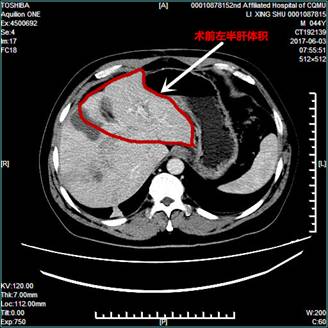

近日,由肝胆外科微创外科团队完成的首例肝癌行ALPPS手术患者回到科室开始第一次TACE治疗。该患者因肝癌误诊为血管瘤未及时治疗(肿瘤已几乎占据右侧肝脏中部),1个月前抱侥幸的希望来到二院肝胆外科就诊。要想得到根治,该患者需要切除右侧半肝。但术前CT检查发现,患者有乙肝肝硬化及脂肪肝的疾病基础,左肝很小,切除右肝后有发生肝衰竭的可能性极大,按照传统治疗方法该患者已丧失手术机会。

在龚建平主任的大力支持下,刘作金教授带领微创外科团队,决定采用目前最先进的ALPPS手术方式解决该难题:也即一期腹腔镜下结扎右侧门静脉,沿左右半肝缺血线劈开左、右侧半肝;待第一次手术后三周,左侧肝脏明显增生后,再次手术切除右侧半肝。